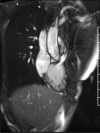

The Society for Cardiovascular Magnetic Resonance (SCMR) is an international society focused on the research, education, and clinical application of cardiovascular magnetic resonance (CMR). Case of the week is a case series hosted on the SCMR website ( https://www.scmr.org ) that demonstrates the utility and importance of CMR in the clinical diagnosis and management of cardiovascular disease. Each case consists of the clinical presentation and a discussion of the condition and the role of CMR in diagnosis and guiding clinical management. The cases are all instructive and helpful in the approach to patient management. We present a digital archive of the 2020 Case of the Week series of 11 cases as a means of further enhancing the education of those interested in CMR and as a means of more readily identifying these cases using a PubMed or similar search engine.